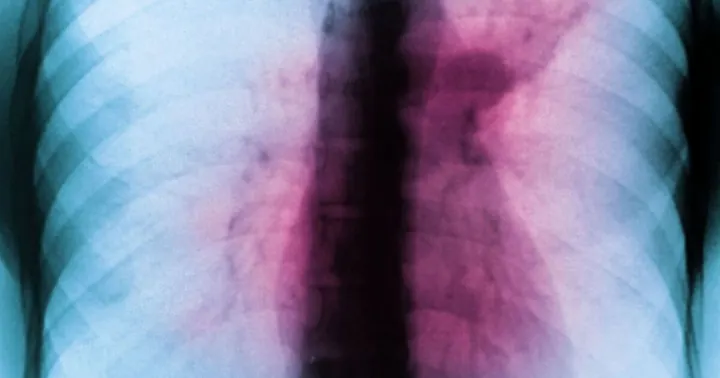

Tuberculosis (TB), known as the 'white plague', is increasingly spreading across the UK and Europe. Recent reports highlight that health services are failing to identify one in five cases of TB in the European Region. This alarming statistic underscores significant gaps in detection and treatment.